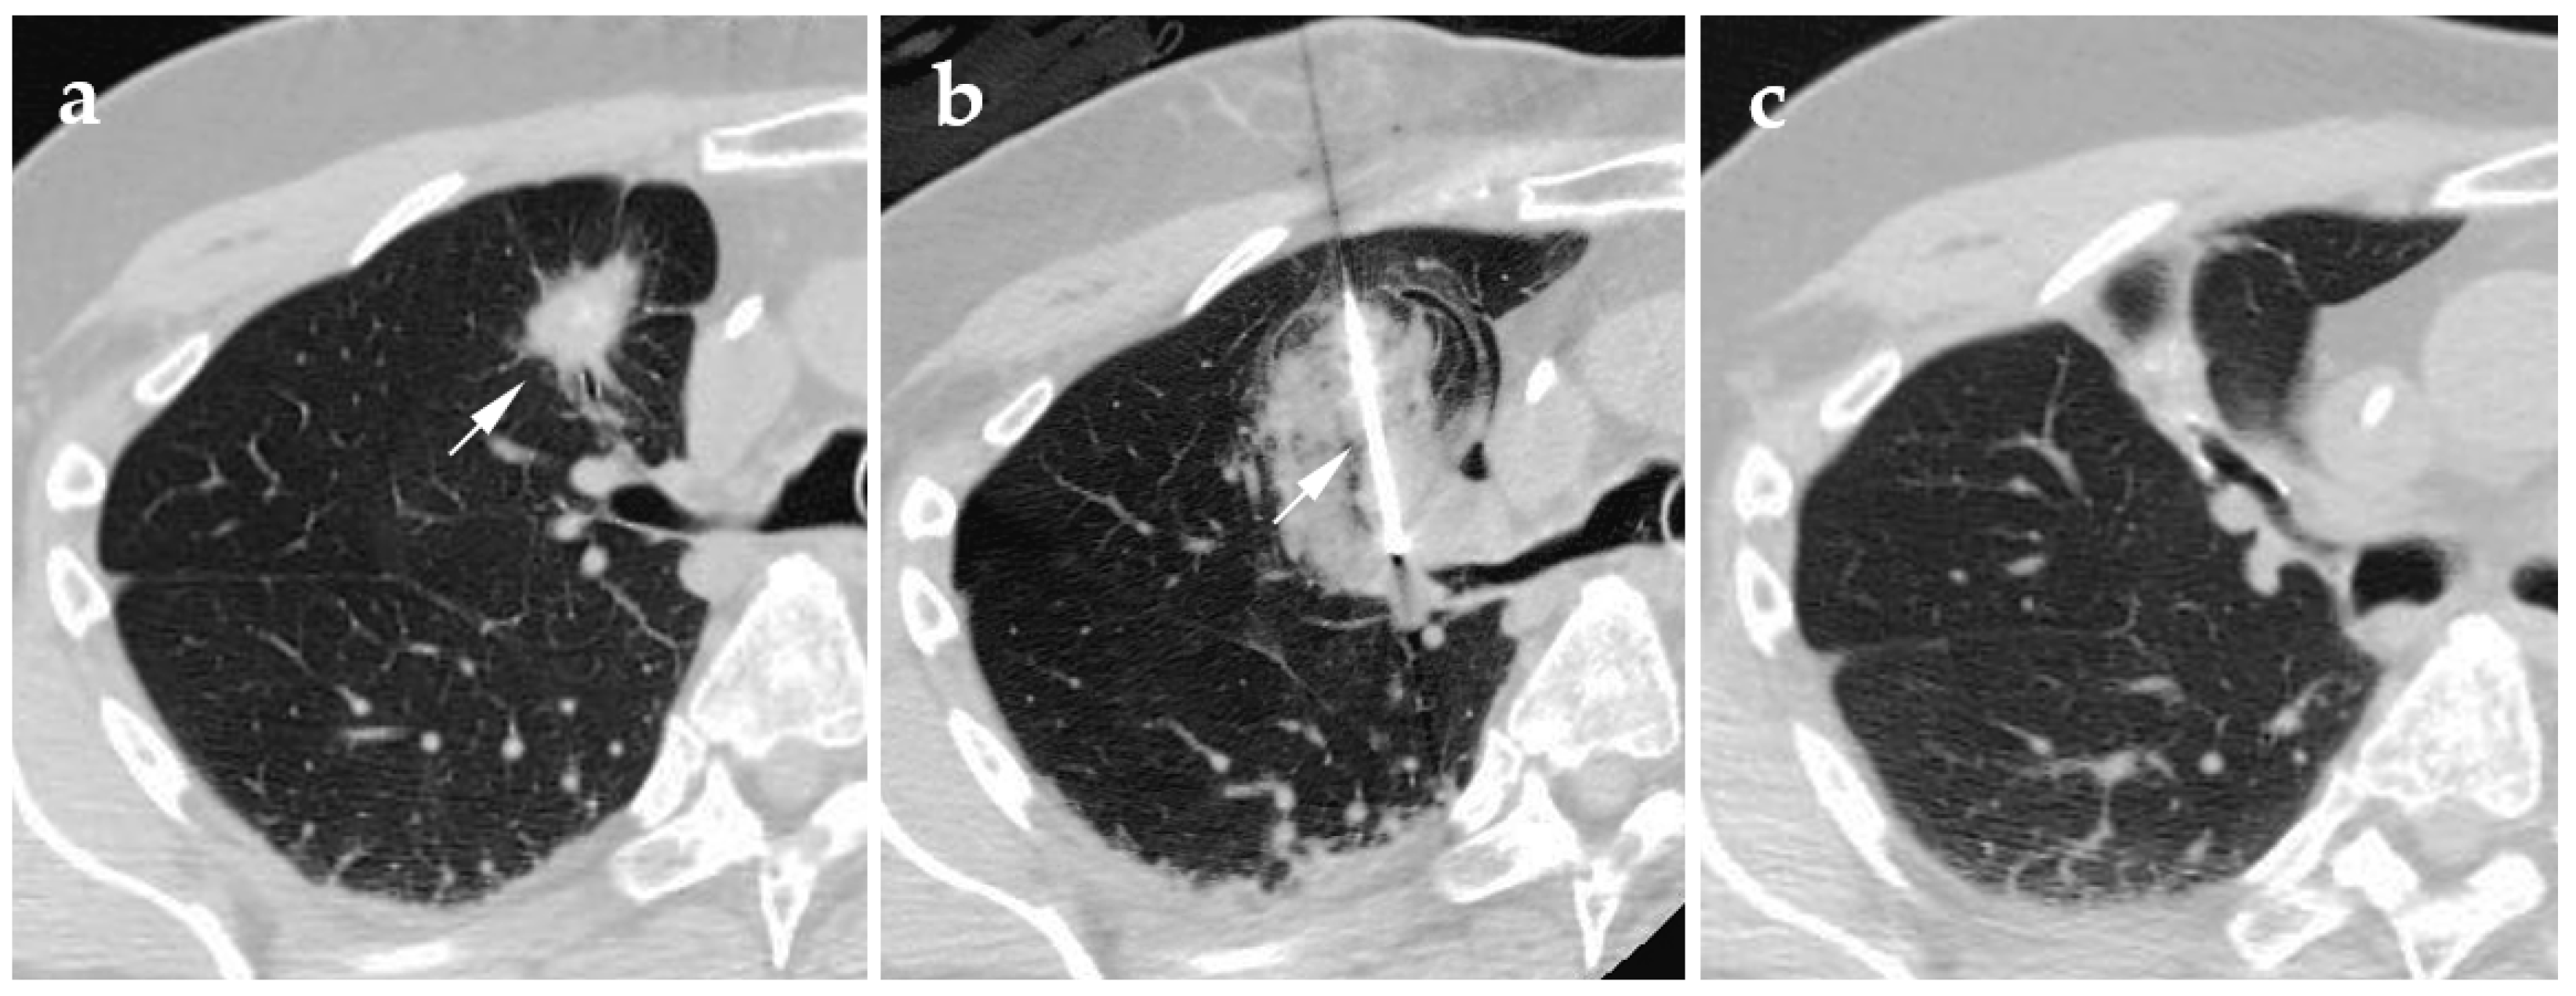

4.1. Cryoablation